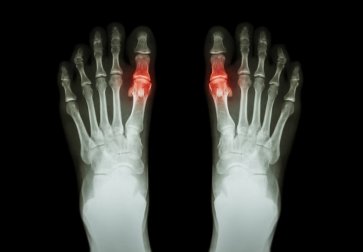

Saiba como tratar os sintomas da gota, uma doença causada pelo acúmulo de cristais microscópicos de ácido úrico nas articulações. Esses cristais formam aglomerados salientes embaixo da pele ou são depositados no trato urinário.

No entanto, quando isso não acontece, o nível de ácido úrico aumenta de forma anormal. Isso se traduz em cristais que são depositados nas articulações, levando a episódios de dor aguda.

- Inicialmente, apenas uma ou várias articulações são afetadas. Geralmente são aquelas do dedão do pé, joelho ou tornozelo.

- A articulação afetada fica quente e corada (inflamada) e geralmente sensível e inchada.

Por fim, podem se desenvolver tofos (nódulos sob a pele ao redor das articulações ou em locais como os cotovelos, pontas dos dedos ou orelhas). Às vezes, substâncias esbranquiçadas podem aparecer, embora apenas naqueles pacientes que tiveram a doença por muitos anos.